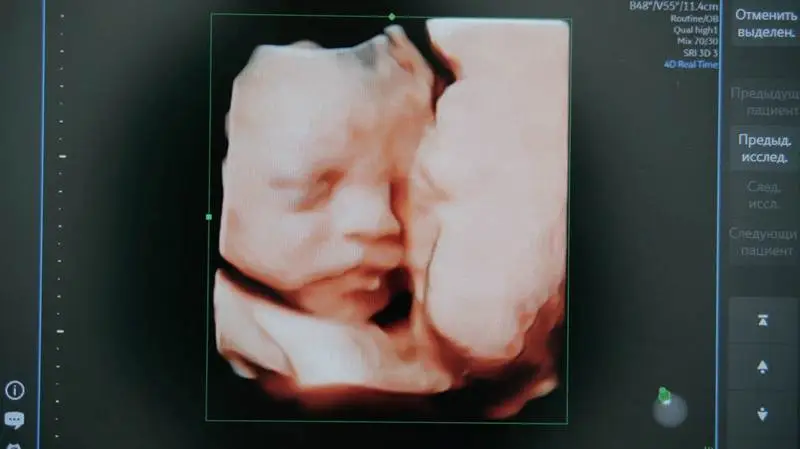

Основой проекта является система искусственного интеллекта, предназначенная для анализа УЗИ-снимков. Технология была разработана на облачной платформе Yandex Cloud и с использованием экспертизы Центра технологий для общества. Она будет применяться при первом скрининге, который проводится на 11—14 неделе беременности.

Система будет анализировать результаты УЗИ беременных с использованием ИИ, обрабатывая только изображения без доступа к персональным данным пациентов. Облачные технологии Yandex Cloud будут использоваться для хранения и обработки данных, а также для обучения нейросетей.

Специалисты подчеркнули, что технологии Yandex Cloud уже применяются в различных социально значимых проектах. Ранняя диагностика spina bifida имеет важное значение, так как это заболевание может привести к серьезным последствиям. Проект также включает экспертов из Национального медицинского исследовательского центра акушерства, гинекологии и перинатологии, где данная технология уже была протестирована.